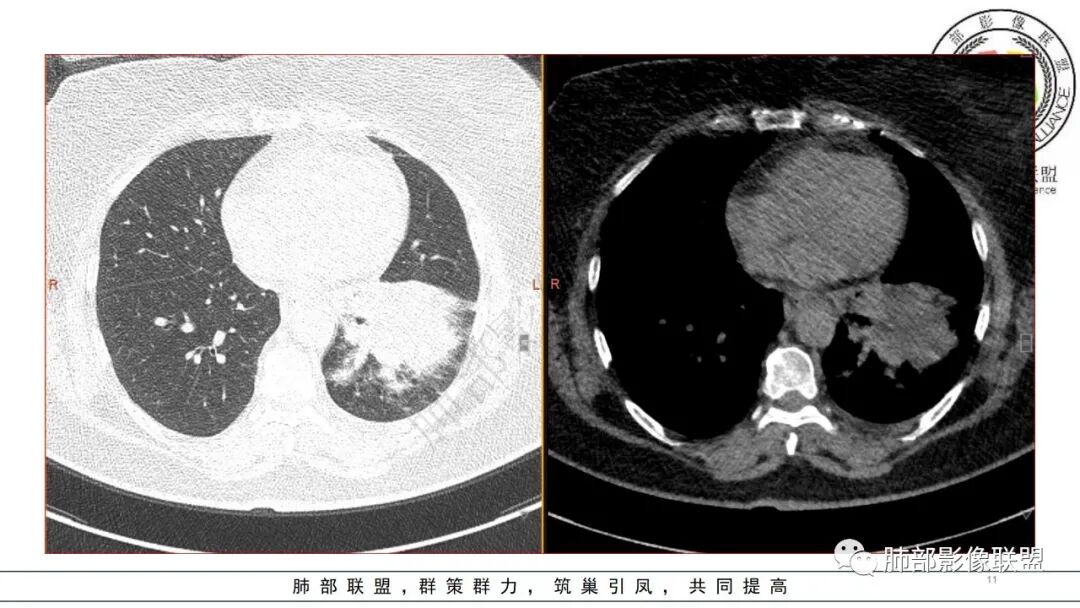

2.左肺下叶大范围实性密度影,散乱,边界不清,可见液化空洞,病变肺体积轻度增大。支气管相关(相应支气管闭塞)。

3.五天后及十三天后病灶变化明显,实性密度影吸收缩小,边界趋于清楚,显示多空腔。

4.肺炎克雷伯杆菌肺炎病灶也易形成脓腔。本例患者未出现典型金葡感染影像学特征,患者临床表现相对“逍遥”缓慢,结合实验室检查,更符合肺炎克雷伯杆菌肺炎。

肺克的鉴别点,肺克多来自血播,所以肺克的典型影像是标准的SPE,SPE的过程中有动态表现,实变-反晕-空洞液化,是一个发展过程。

金葡应该也是血源性来源,因此也存在鉴别,区别在肝脏,肺克的血播是肝脏来源,金葡的血播可以各种来源,但是一般不会是肝脏来源,具体来说,金葡的SPE观察不那么典型,金葡可以形成更大的实变,肺克少一些,金葡的特征应该还是气囊,壁的张力更高,更薄,SPE似乎不明显,临床上皮肤软组织脓肿的有无,这个特征肺克应该不具有,但肺克一般有肝脓肿,没有的少见。